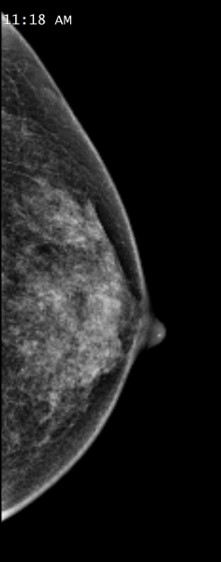

2D低疼痛乳房造影

乳房造影為專為乳房而設的高解像度 X 光檢查。這是一種普遍的乳房癌症篩選檢查。篩查是指為沒有症狀的人士進行檢測,從而找出患病或有較高風險患病的人。

本中心採用嶄新的低輻射數碼乳房 X光造影儀器 MAMMOMAT Inspiration。它能自動計算壓迫力度,在獲得影像後便停止壓迫乳房,大幅減少檢查時的不適感。另外,它的最新數位式平板接收器能根據個別乳房的大小及組織類型計算劑量,以確保使用最低輻射劑量。每張影像拍攝過程只需數秒。